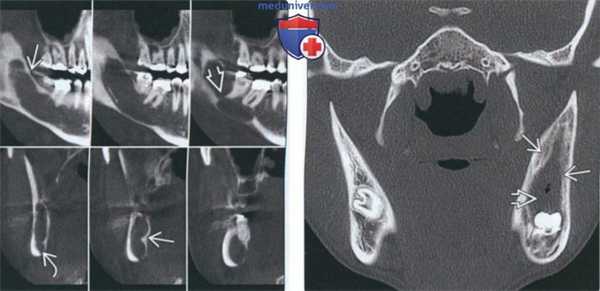

(Слева) На кадрированной панорамной рентгенограмме определяется большая ОКК вокруг коронки смещенного импактного третьего моляра нижней челюсти, занимающая ветвь целиком. Края выглядят фестончатыми внутри кисты визуализируются несколько небольших перегородок.

(Справа) На аксиальной КТ в костном окне у этого же пациента определяется гиподенсная киста, приводящая к вздутию язычной кортикальной пластинки нижней челюсти. Определяется периостальная реакция вдоль щечной кортикальной пластинки, означающая вторичную инфекцию.

(Слева) На сагиттальной КЛКТ (под углом) и профильных срезах определяется ОКК в виде хорошо отграниченного гиподенсного кистозного образования с фестончатыми краями и единственной перегородкой внутри. Вздутие выражено минимально, но нижнечелюстной канал смещен книзу.

(Справа) На корональной КТ в костном окне определяется ОКК, подвергнутая марсупиализации. Определяются костные наслоения, заполняющие кисту, начиная с кортикальных пластинок на периферии (в области, где осущеавлялось вмешательство) с наличием дефекта минимального размера.

(Слева) На кадрированной панорамной рентгенограмме в задних отделах нижней челюсти слева визуализируется рентгенопрозрачная одонтогенная кератокиста (ОКК), четко отграниченная кортикальной пластинкой. Перегородки придают кисте вид многокамерной. Обратите внимание на легкую резорбцию корня первого моляра.

(Справа) На корональной КТ в костном окне у молодой женщины визуализируется большая ОКК, занимающая задние отделы и ветвь нижней челюсти. Определяется вздутие кортикальных пластинок, но рост выражен преимущественно вдоль костной ткани, а не в наружно-внутреннем направлении. Кортикальные пластинки становятся фестончатыми, имеет место перфорация. (Слева) На окклюзионной и периапикальной рентгенограммах визуализируется ОКК, проникающаяся между зубов и воздействующая на щечную кортикальную пластинку нижней челюсти. Эти признаки также характерны для простой костной кисты; тем не менее, смещение зубов и резорбция твердой пластинки позволяют заподозрить более агрессивное поражение.

(Справа) На аксиальной КТ в костном окне у этого же пациента определяется распространение поражения вдоль нижней челюсти в отсутпвие значительного вздутия. Эти изменения характерны для ОКК. Внутри кисты также визуализируются включения повышенной плотности.